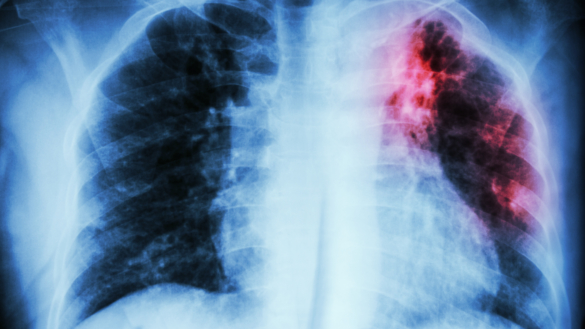

Tuberkulos, TBC, är en infektionssjukdom som främst påv...